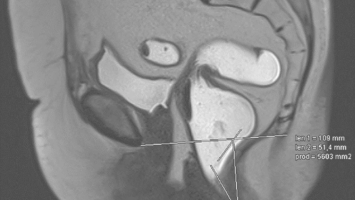

Vergleich von MR-Defäkographie und klinischer Untersuchung

In der Diagnostik von Deszensusprozessen kommt, neben der klinisch-proktologischen Untersuchung, regelmäßig eine MR-Defäkographie als aufwendige und kostenintensive Diagnostik zum Einsatz. In diesem Beitrag wird dargestellt, inwieweit bei …

Springer Medizin Podcast - Endometriose/© (M) Willer D. et al. / all rights reserved Springer Medizin Verlag GmbH Logo: Springer Medizin Verlag GmbH, Ärztin misst Blutdruck bei Schwangeren/© Andrey Popov / Stock.adobe.com (Symbolbild mit Fotomodell), Schwangere Frau hält Tablette und Glas Wasser/© NDABCREATIVITY / stock.adobe.com (Symbolbild mit Fotomodell), Justiz/© hawi_101 / Fotolia, CT des Uterus einer 47-Jährigen /© Rizos A et al. | all rights reserved Springer Medizin Verlag GmbH, Gardnerella spp. bedeckte Schlüsselzellen/© Swidsinski A et al. / all rights reserved Springer Medizin Verlag GmbH, Impfung/© Remains / Getty Images / iStock (Symbolbild mit Fotomodellen), Junge Frau sitzt auf Toilette/© Dragana Gordic / stock.adobe.com (Symbolbild mit Fotomodell), Spritze wird aufgezogen/© scyther5 / Getty Images / iStock, Ultraschall der "kissing ovaries" bei Endometriose/© Willer D. et al. / all rights reserved Springer Medizin Verlag GmbH, Ärztin führt Ultraschall bei einer Frau durch/© satyrenko / stock.adobe.com (Symbolbild mit Fotomodellen), Doxy-PEP/© Tobias Arhelger / stock.adobe.com, Junge Frau zur Beratung bei Ärztin/© demaerre / Getty Images / iStock (Symbolbild mit Fotomodellen), Schwangere macht Gymnastik/© fotostorm / Getty Images / iStock (Symbolbild mit Fotomodell), Junge Patientin im Gespräch mit einer Ärztin/© FatCamera / Getty Images / iStock (Symbolbild mit Fotomodellen), Urogenitale Fistel bei einer 36-jährigen Patientin/© Lautenschlager S et al. / exklusiv lizenziert an Springer-Verlag GmbH Austria, ein Teil von Springer Nature 2024, CT bei endometrioidem Karzinom/© Kuzinska MZ et al. / all rights reserved Springer Medizin Verlag GmbH, Frau nimmt Diaphragma in der Hand/© AndreyPopov / Getty Images / iStock (Symbolbild mit Fotomodellen), Ein Abstrich vom Gebärmutterhals wird auf ein Objektivträger geschmiert/© Tatiana Buzmakova / Getty Images / iStock (Symbolbild mit Fotomodellen), Frau nutzt Pen am Bauch/© bung / Stock.adobe.com (Symbolbild mit Fotomodell), Reife Eizelle im Mikroskop/© S. Al-Hasani, Podcast mit Partnern - Roche STI/© (M) Aleksej / stock.adobe.com; Logo: Springer Medizin GmbH, Titelbild Kongress Kompakt EADV 2024/© Hintergrundbild: gnoparus / stock.adobe.com, Search Icon, Paar schaut glücklich auf Schwangerschaftstest/© Andrii Zastrozhnov / Stock.adobe.com (Symbolbild mit Fotomodellen), ZFA TALKS - Depression/© (M) seb_ra / Getty Images / iStock (Symbolbild mit Fotomodell) Logo: Springer Medizin Verlag GmbH, Ältere Frau fasst sich an die Brust/© Jelena Stanojkovic / Stock.adobe.com (Symbolbild mit Fotomodell), Person setzt DNS-Probe in Maschine ein/© Vit Kovalcik / stock.adobe.com